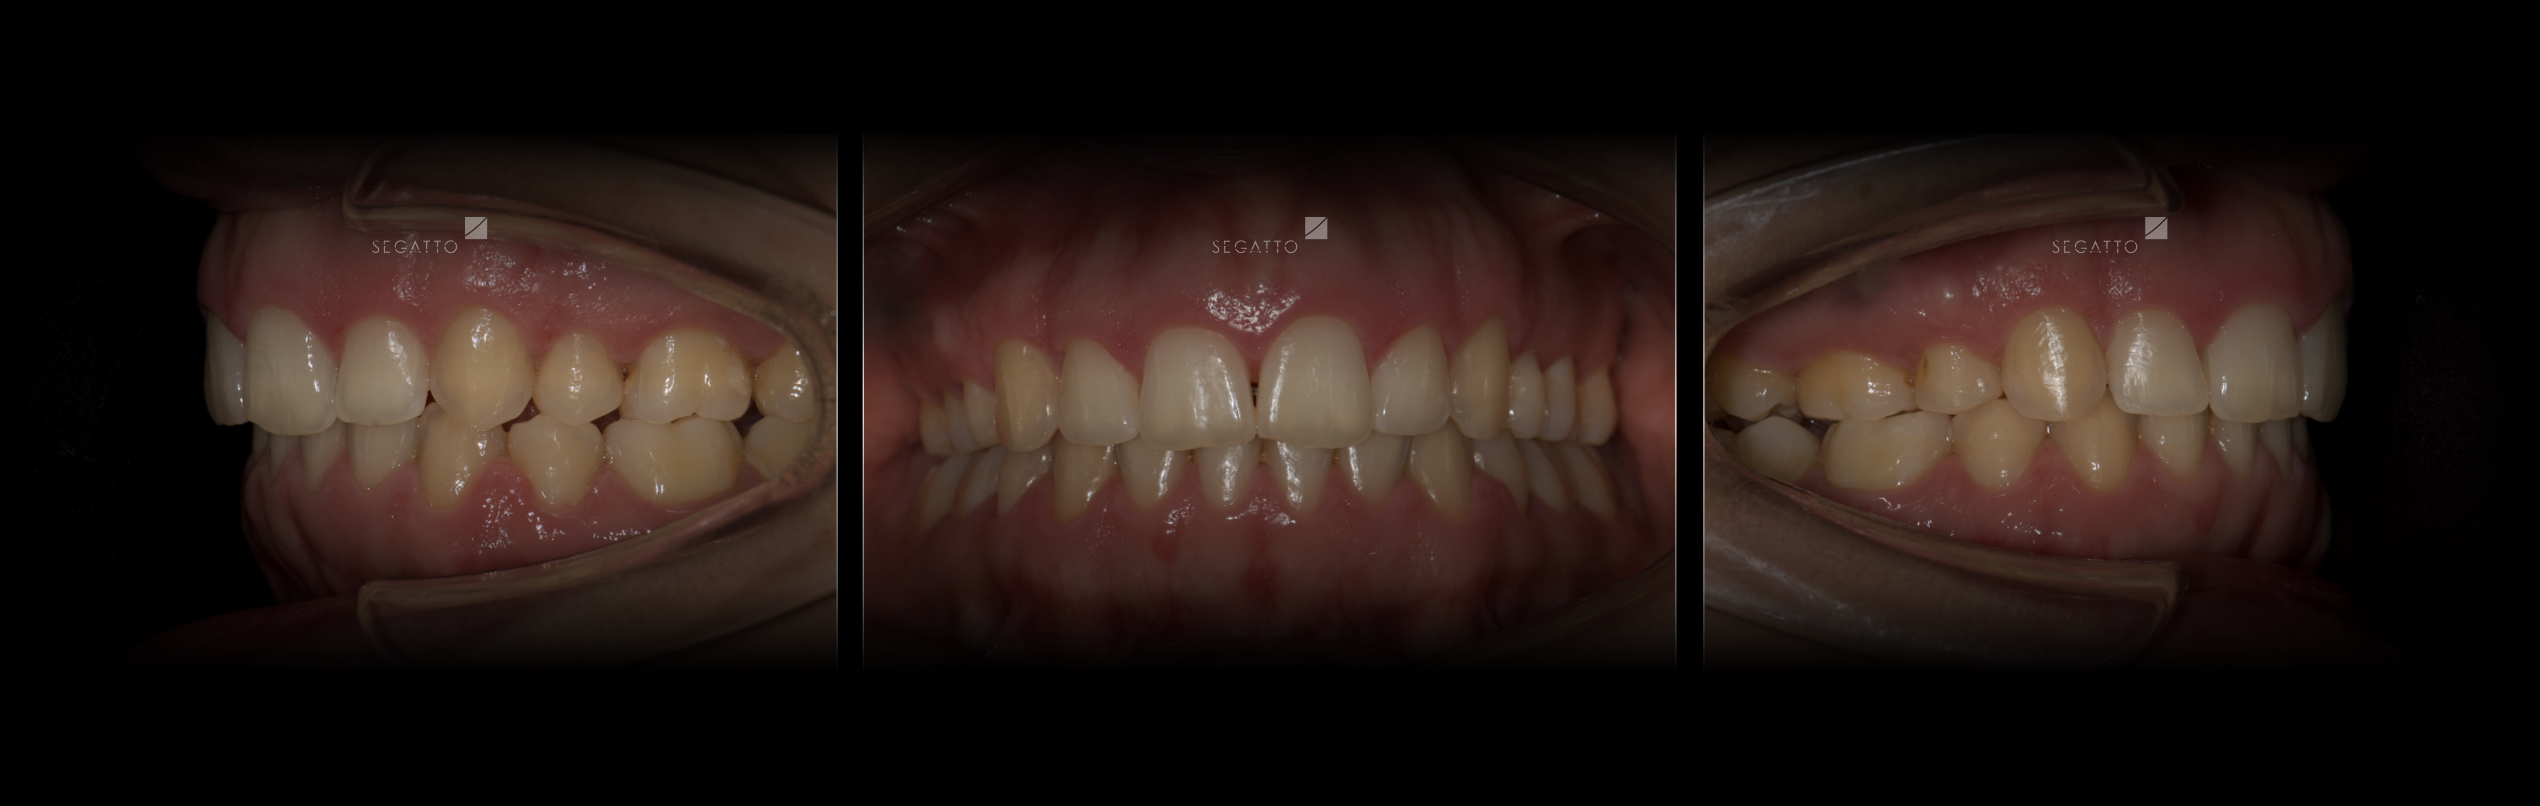

Orthodontics

Cases